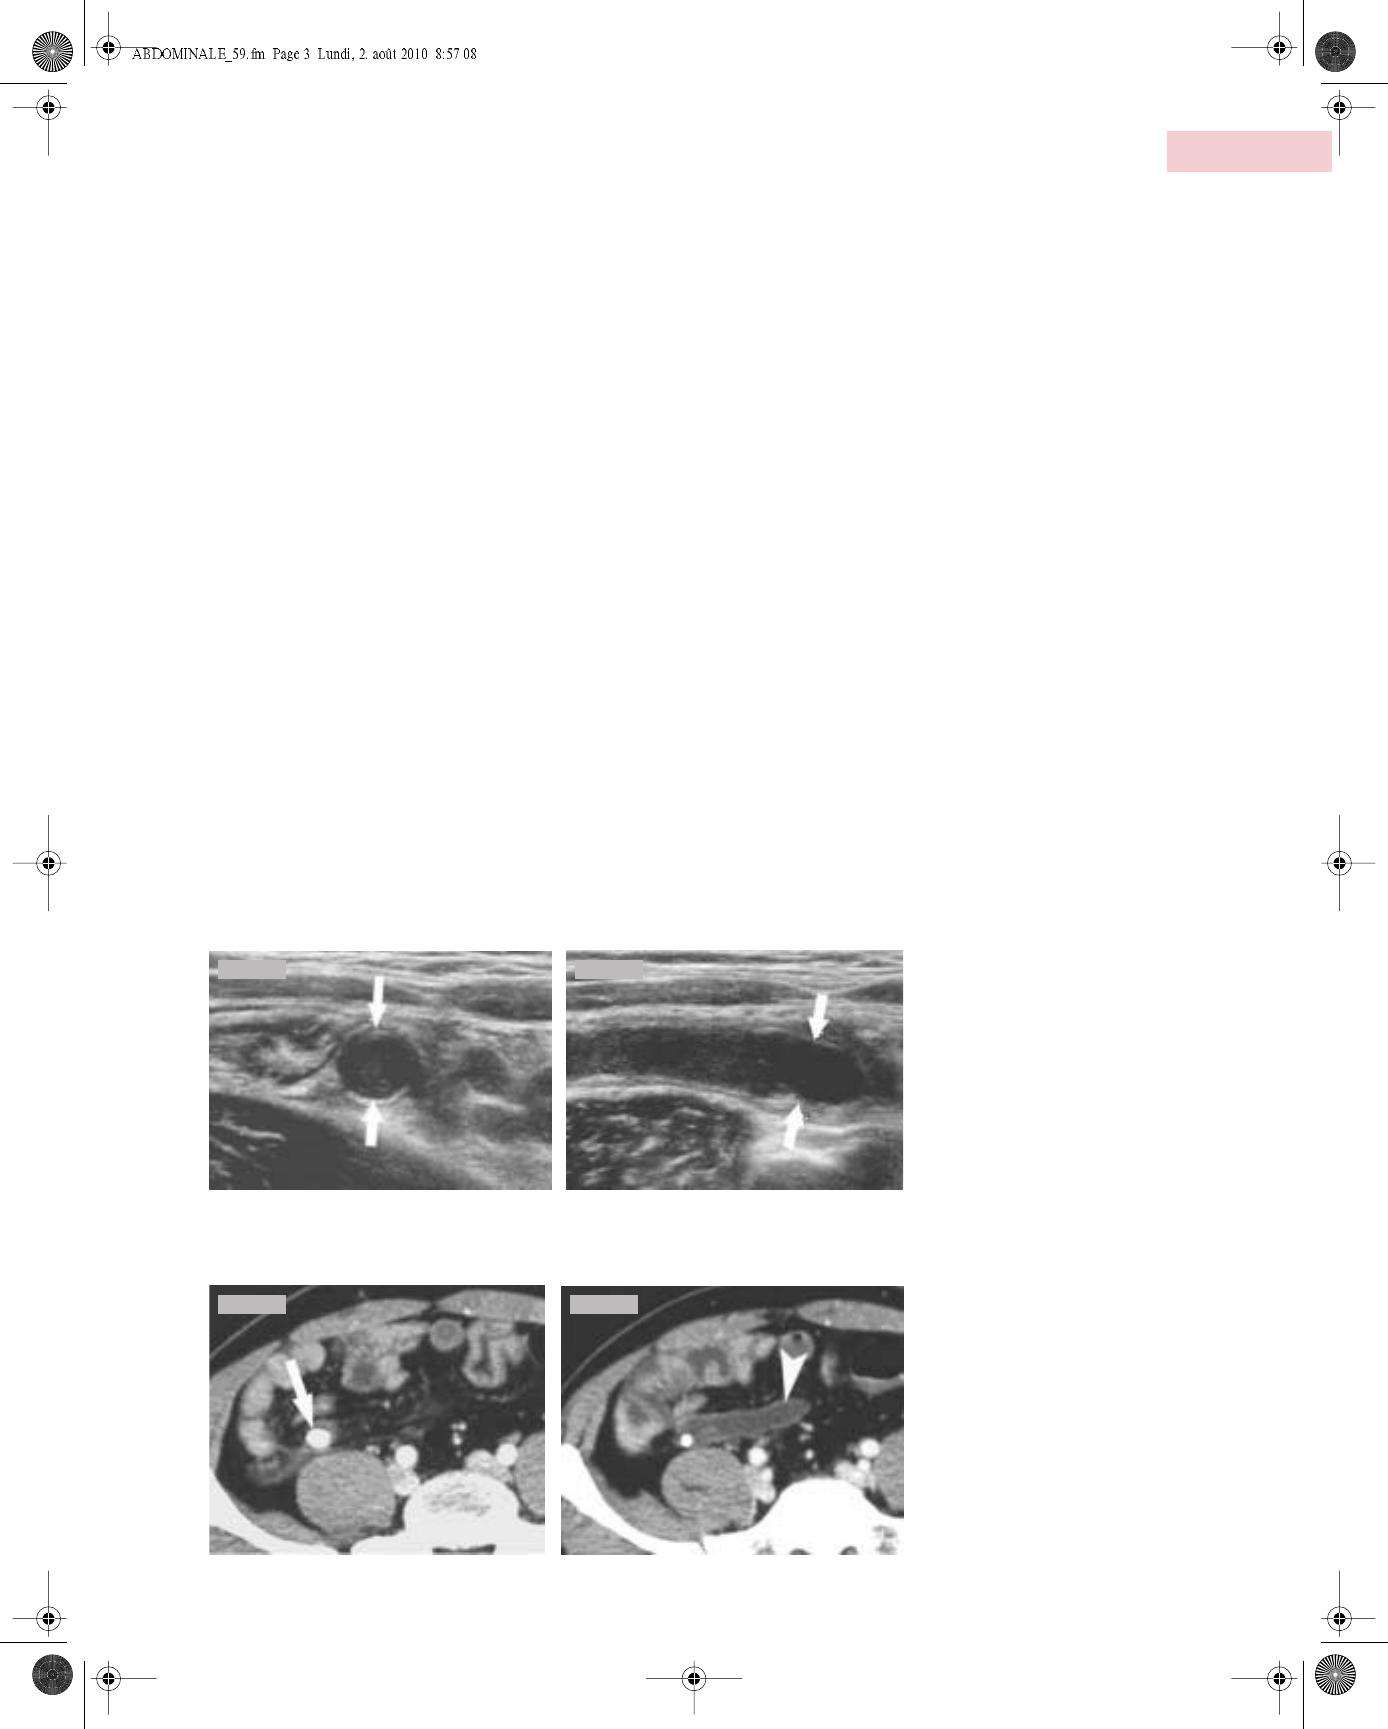

L’échographie haute résolution (5 à 12 MHz) permet d’individuali-

ser les différentes couches de la paroi digestive, d’évaluer le péris-

taltisme et d’explorer avec précision la zone de douleur maximale.